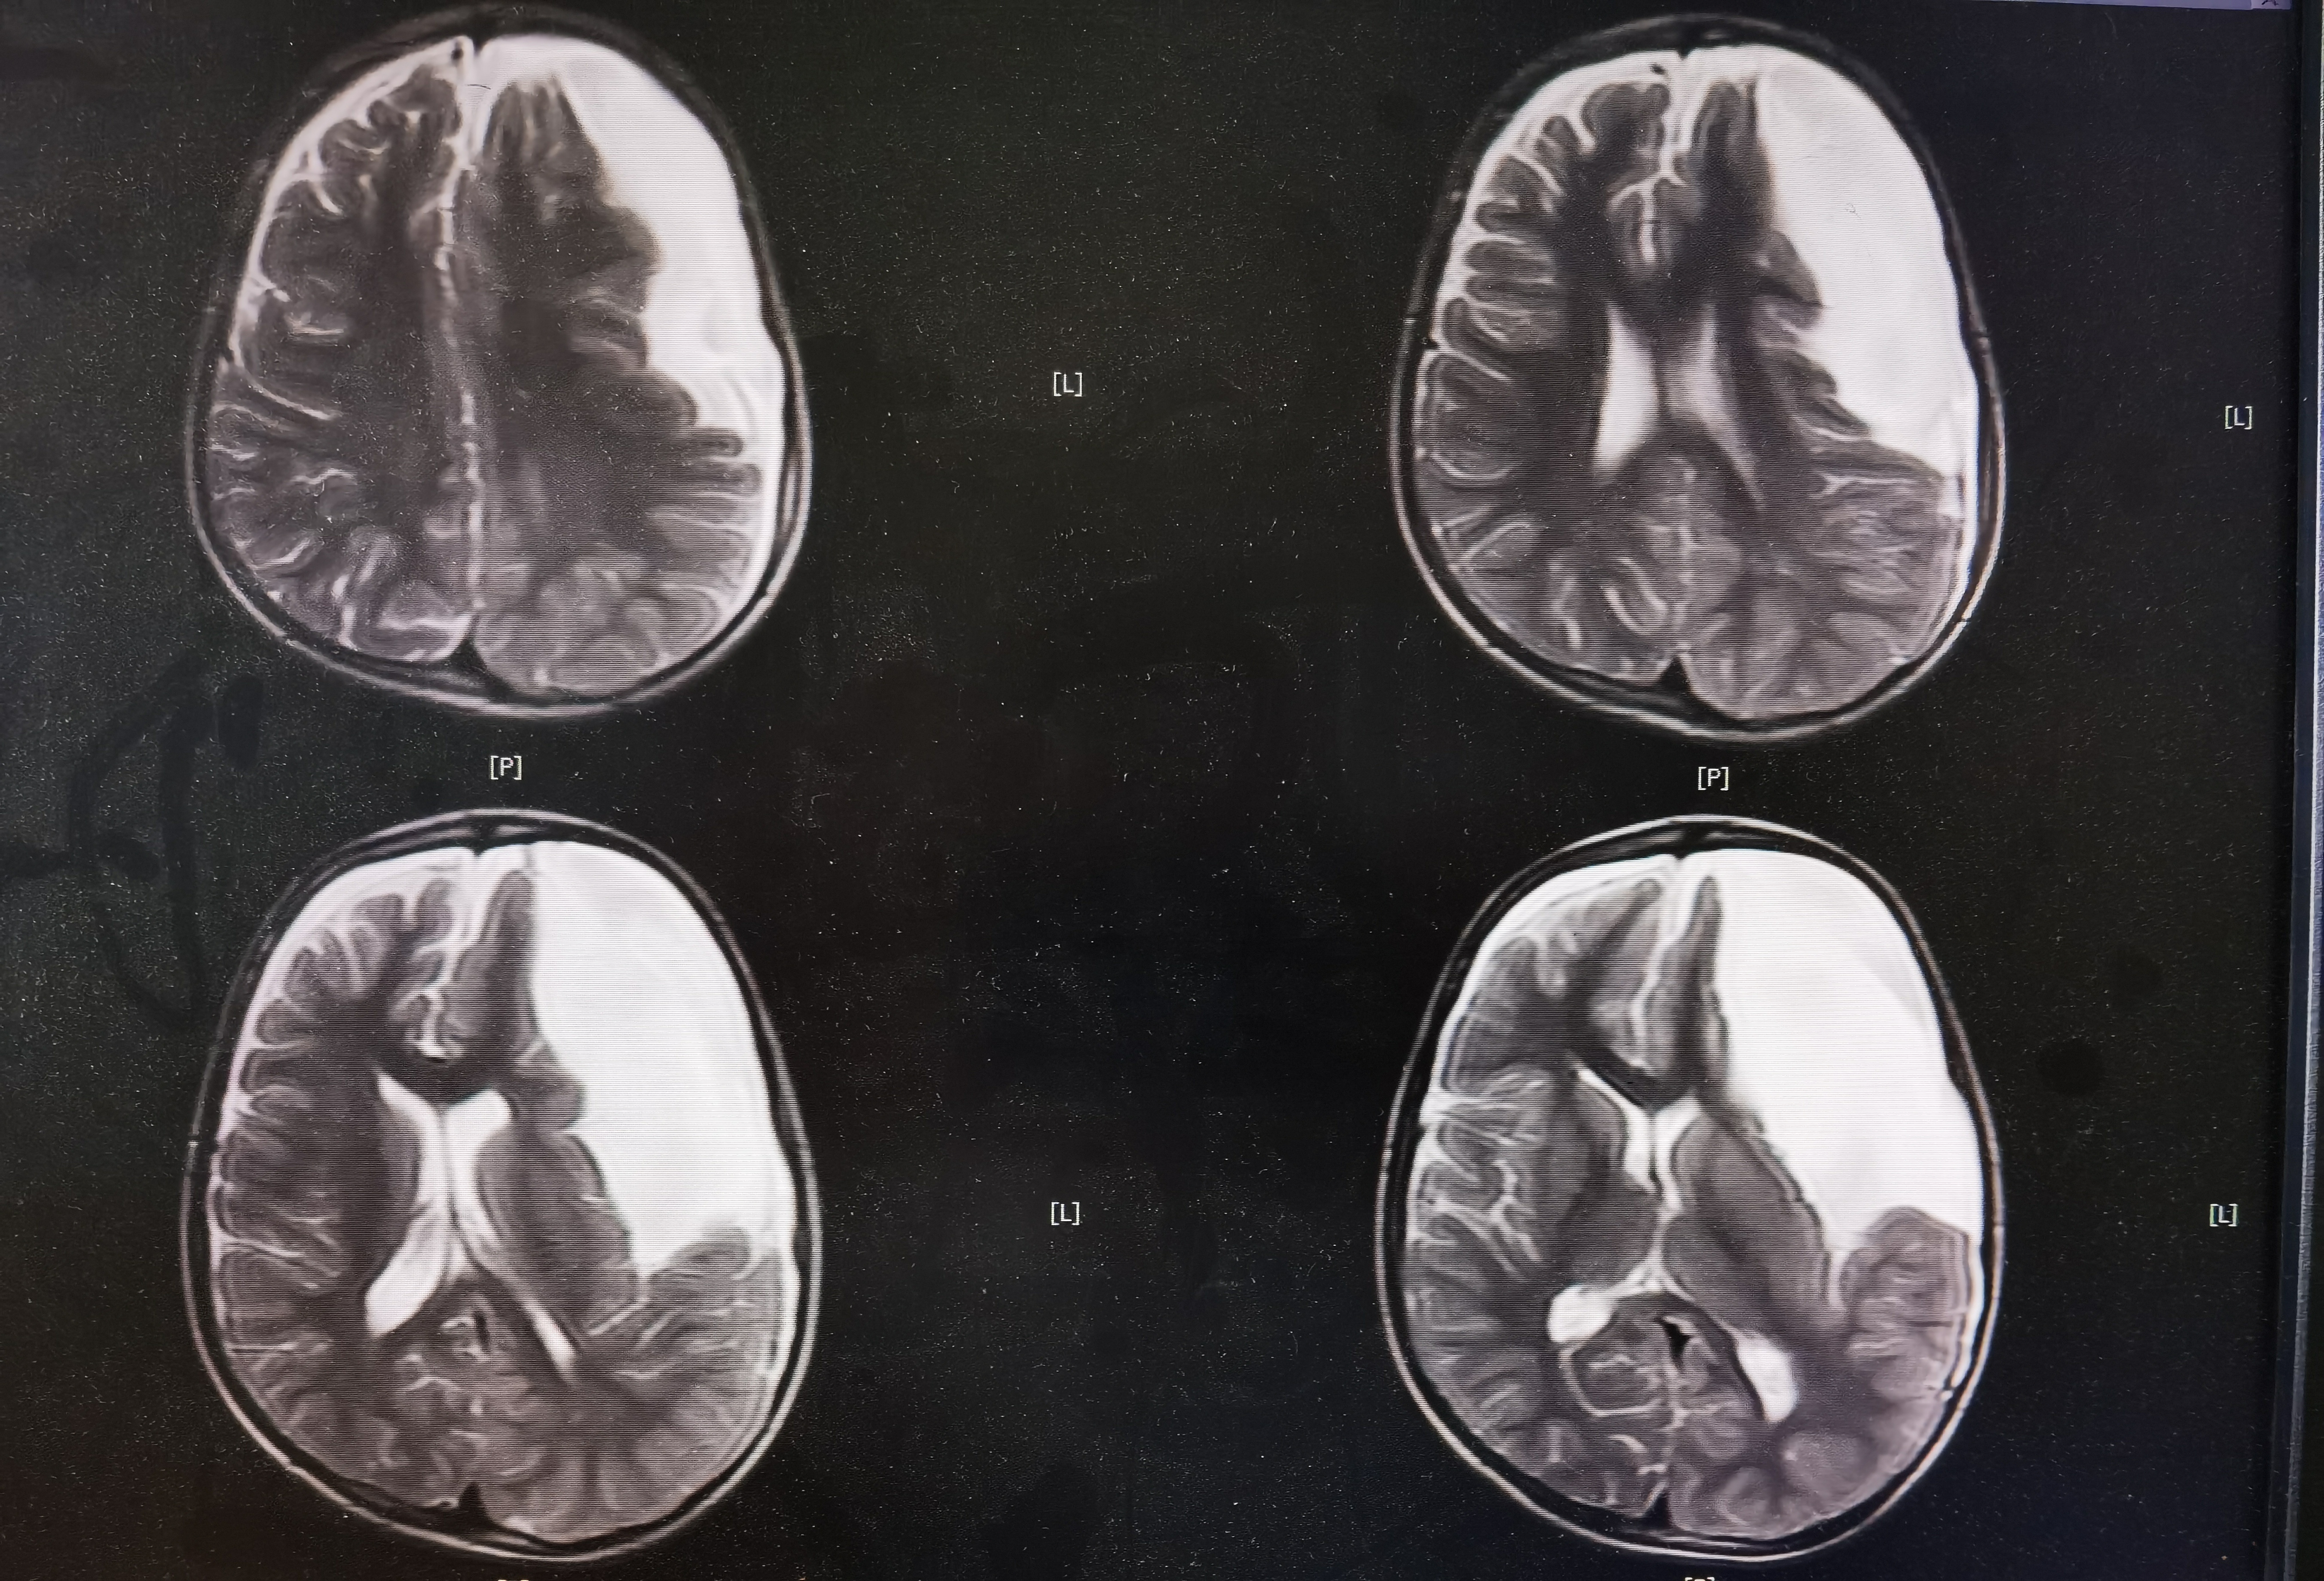

8岁男孩,以“头部外伤后头晕8天”入院,患儿8天前于3米高处坠落摔伤头部,伤后有昏迷史,当地医院CT提示左额颞巨大蛛网膜囊肿,破裂可能。患儿伤后感头晕,当地医院建议转至我院。我院完善头颅MR提示左额颞巨大蛛网膜囊肿,局部越过中线突入右侧镰旁挤压右额叶,左侧额颞岛叶明显受压,囊肿破裂可能。

术前MR